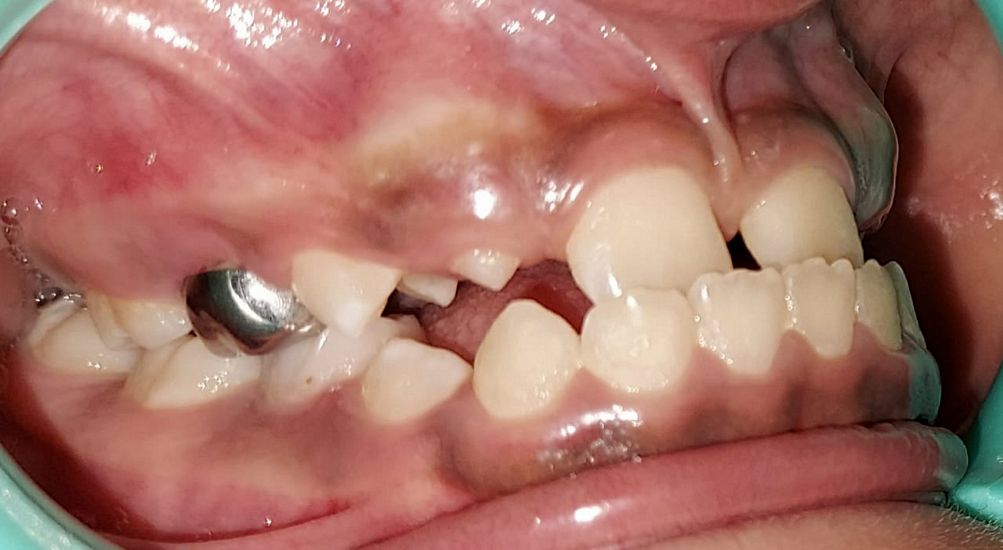

Intra-oral : Pre-treatment : Right Lateral View